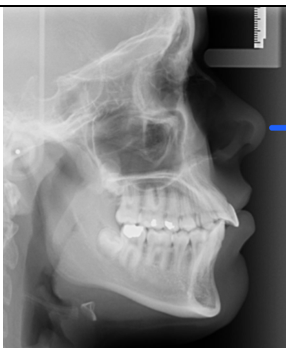

Name this type of radiograph

Cephalometric